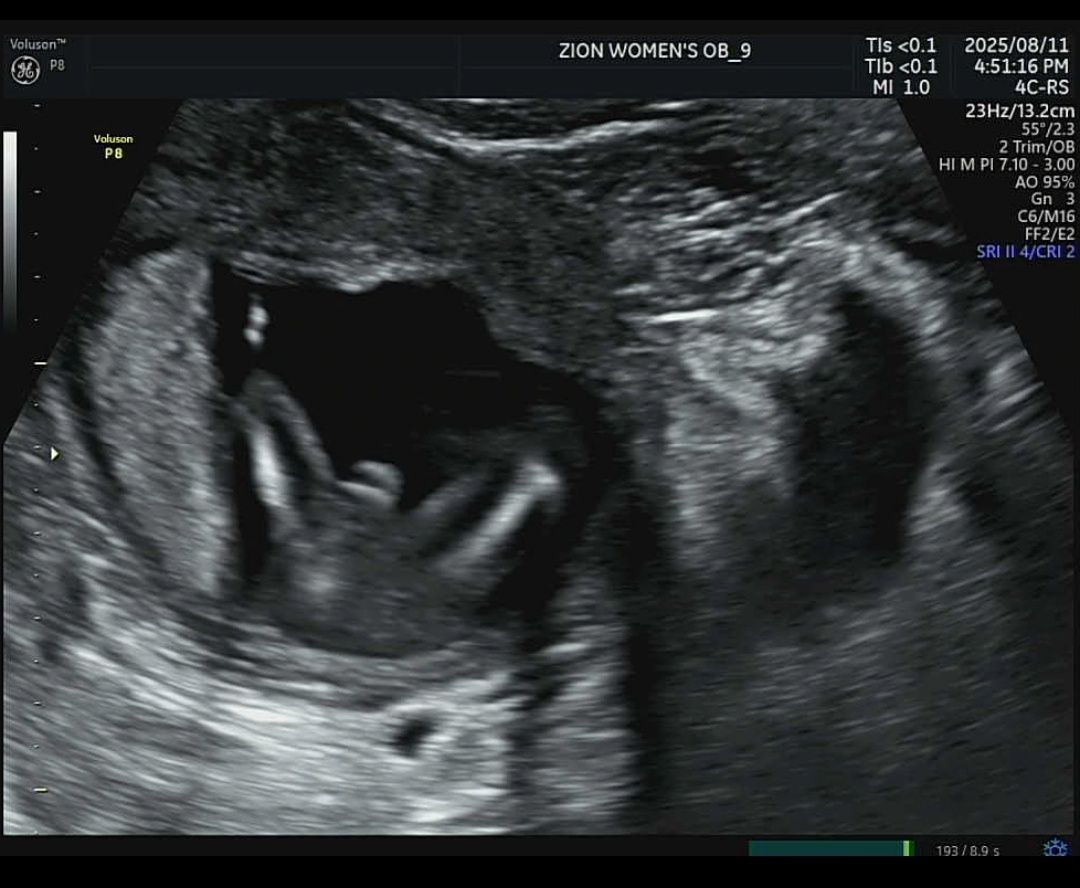

둘째 임신하고 성별 보러갔는데 자세가 너무 구석에 웅크리고있어서 생식기가 잘 안보이신다고 하시다가 겨우 보시고 아들일꺼같다곤 하셧는데 성별 반전있을까요? 첫째가 아들인데 첫째때랑 느낌이 너무 달라서요

아들 같아 보이지는 않는데요 ㅠ 고추 저모양은 약간 끝이 뾰족해요

아들같아요